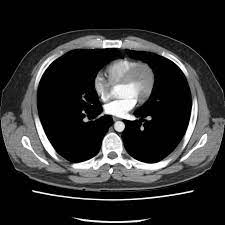

Black Hole In The Lung Bone Marrow Transplantation

Black Hole In The Lung Bone Marrow Transplantation from media.springernature.com

This video tutorial discusses ct scans in the context of anatomy:0:00. My guess would be some type of fungal infection or cancer. Scan during the arterial phase. This ct scan of the upper chest (thorax) shows a malignant thyroid tumor (cancer). Get a 14.234 second chest ct scan ( thorax stock footage at 30fps. Ct scan of the chest (thorax). Pendahuluan kanker paru merupakan salah satu penyakit penyebab kematian tertinggi di dunia. After reading your post, i would not think it is sarcoidosis.